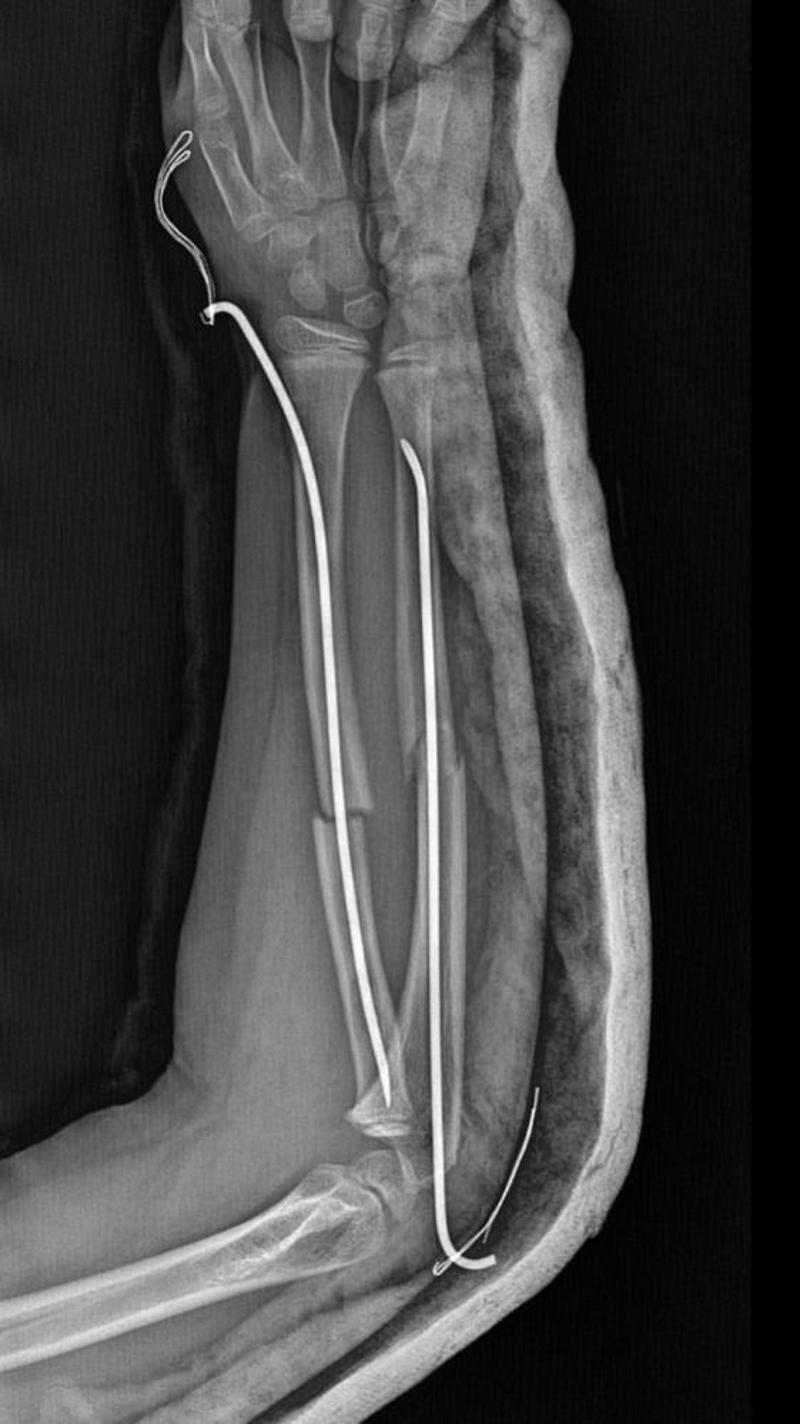

Y.K.Ş.'nin 2'ye katlanan kolu 2 ayrı yerinden kırıldı. Öğretmenler Y.K.Ş.'nin ailesini arayarak, 'oğlunuz arkadaşıyla kavga etti duvara çarptı' denildi. Oğlunu okuldan alıp hastaneye götüren anne Songül Gökdemir, oğlunun kolunun 2 ayrı yerinden kırıldığını öğrenip ameliyata alınacağını duyduğunda büyük şok yaşadı. Konuyla ilgili anne Gökdemir savcılığa giderek şikayetçi oldu. Savcılıktan ise 'söz konusu Suça Sürüklenen Çocuğun yaşının 12'den küçük olduğu gerekçesi ile kovuşturmaya yer yoktur' kararı çıktı. Anne Gökdemir karara itiraz ederken mağdur Y.K.Ş. ise haftalardır okula gidemiyor. Eğitimi aksayan çocuğun 2 hafta sonra ise platinlerinin çıkarılması için yeniden ameliyata gireceği öğrenildi.

Yaşanan olayı anlatan Songül Gökdemir, " Arkadaşlarından darbe aldığını biliyordum. Ayrıca Eylül ayından bu yana bir arkadaşının onun kolunu kırmaya çalıştığını söyledi. Ben de 'arkadaşını öğretmene söyle' dedim. Bundan kaçıyordu. O gün de rehber öğretmenine bu arkadaşını şikayet ettiler. Ben işe gittim 1 saat sonra öğretmeni aradı. Oğlunuz arkadaşıyla birbirini itekledi kolunu duvara çarptı gelir misiniz ?' dedi. Kendi imkanımla hastaneye götürdüm. Okula gittiğimde de oğlum derste oturuyordu. Öğretmen ders işliyordu ambulans çağırılmamış. Hastanede kolunda 2 tane kırık olduğunu acilen de ameliyata girmesi gerektiğini öğrendim. 3 gün sonra ameliyata alındı. Kolundaki platinlerden dolayı her gün pansumanı var. 2 hafta sonra tekrar ameliyatı var" dedi.